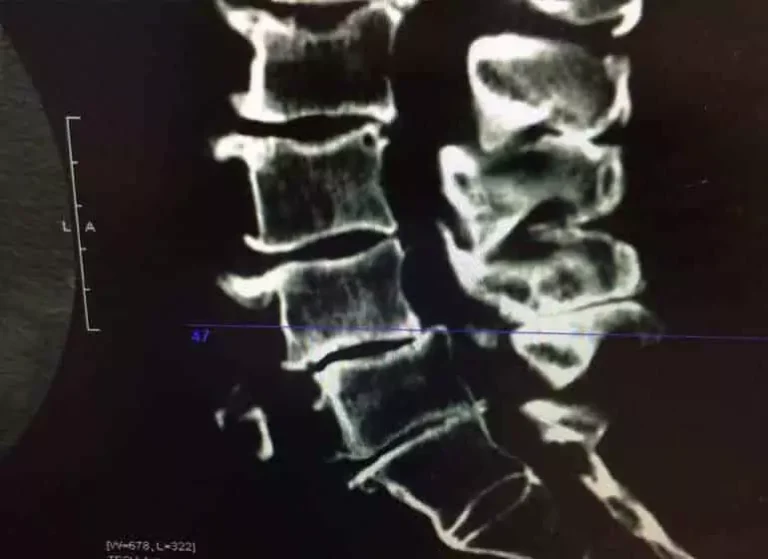

An x-ray imaging of a spine.

Stenosis

Depending on the severity of symptoms, we offer noninvasive treatment options that help to get our patients back into the business of living as pain free as possible. From physical and occupational therapy, to chiropractic care and massage, we’re focused on relief, with increased functionality and mobility.

Learn more about Stenosis.